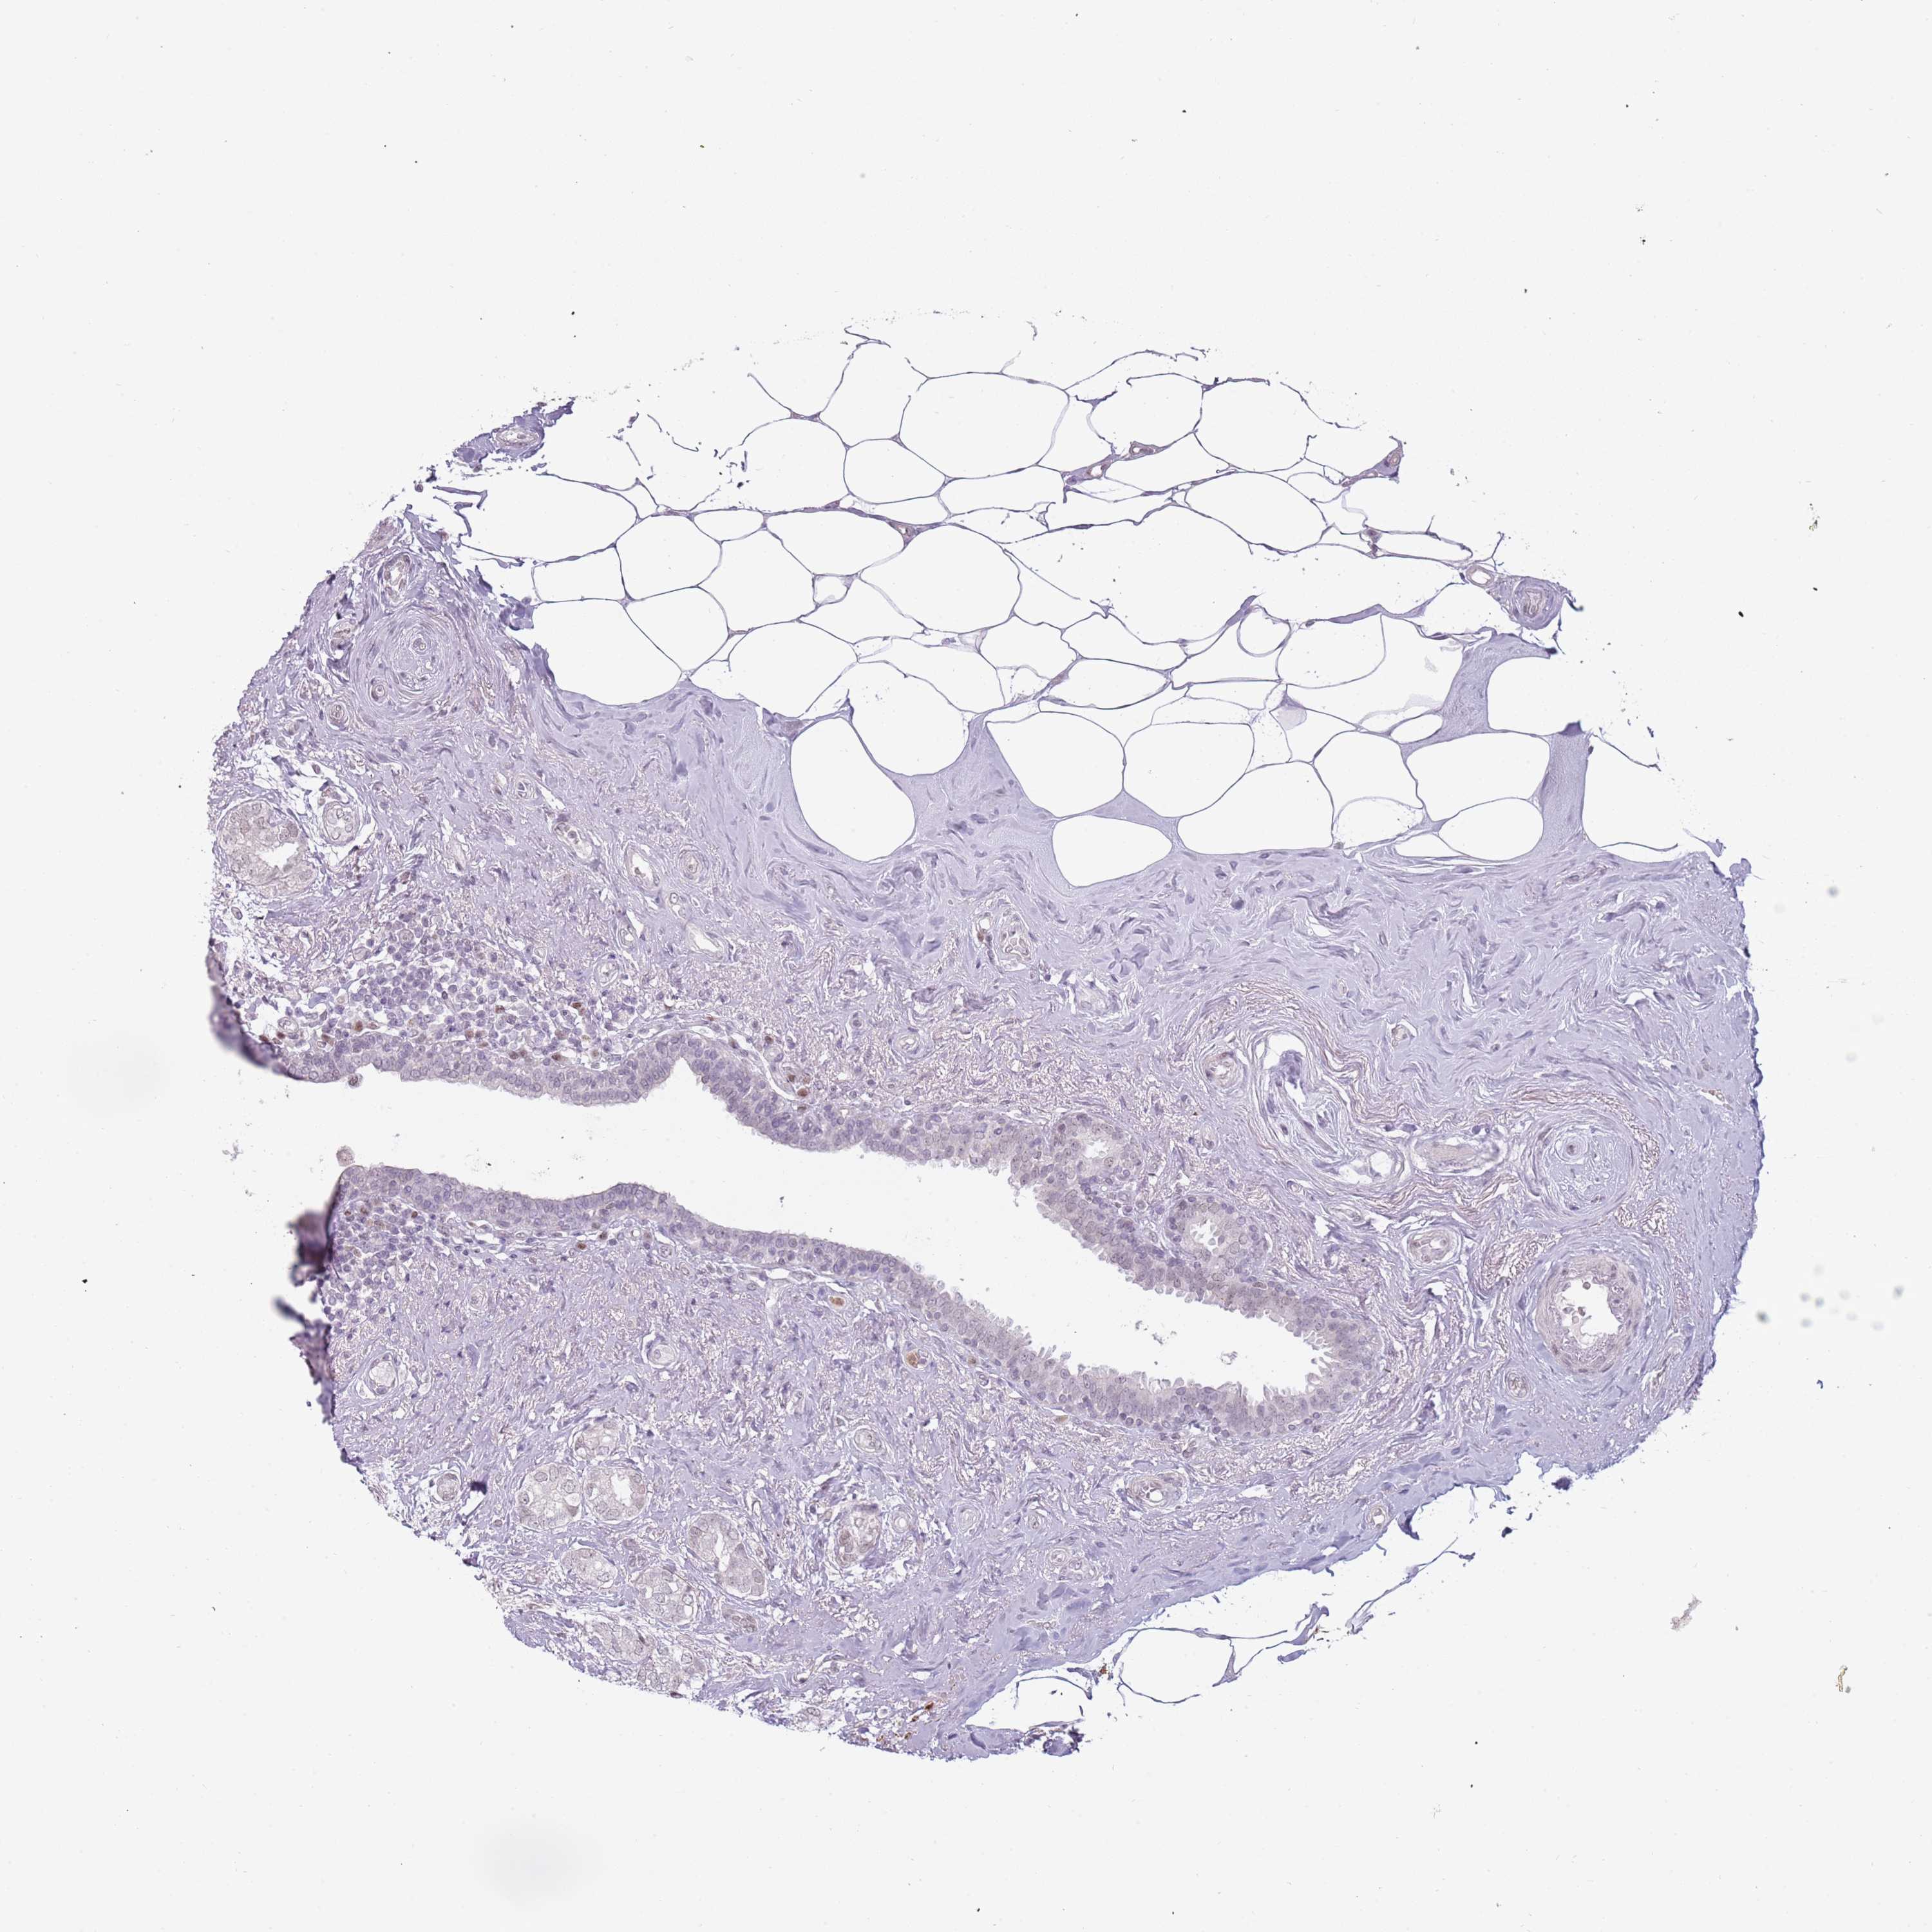

Breast cancer

Human cancer